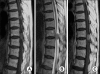

Methods: The spinal IDEM tumor patients (11 cases) who had been treated by surgical excision and who were followed up more than 1 year were retrospectively analyzed. Pain was evaluated by the visual analogue scale (VAS) and the neurologic function was assessed by Nurick's grade. The pathological diagnosis, the preoperative symptom duration, the tumor location on the sagittal and axial planes and the percentage of tumor occupying the intradural space were investigated. In addition, all these factors were analyzed in relation to the degree of the preoperative symptoms and the prognosis. On the last follow-up, the MRI was checked to evaluate whether or not the tumor had recurred.

Conclusions: The degree of neurologic symptoms was correlated with the percentage of tumor occupying the intradural space. All the tumors were able to be excised through the posterior approach. The postoperative neurologic recovery was excellent in all the cases regardless of any condition. Therefore, aggressive surgical excision is recommended even for cases with a long duration of symptoms or a severe neurologic deficit.